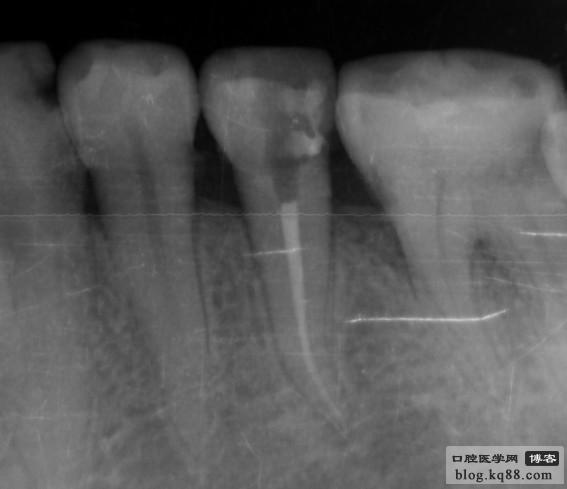

右下5